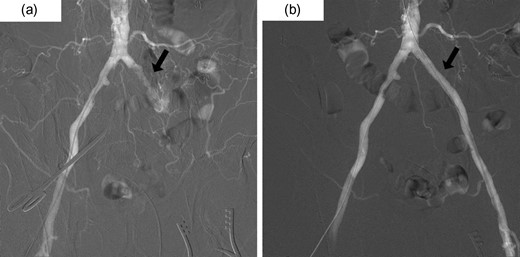

A 70-year-old man underwent a colonoscopy after having episodes of bright red stool per rectum and diarrhea. A lower rectal cancer was diagnosed based on a histology obtained through a biopsy of the rectal lesions (Rb, T2N0M0 cStageI (UICC Classification, 7th ed)). The past medical history was notable for hypertension untreated and smoking 50 pack year. His height was 173 cm, and weight was 73 kg with body mass index of 24.4. The creatinine clearance was 87 ml/min. Although the preoperative history talking failed to recognize the symptoms of intermittent claudication and sensory impairment of his lower extremities, a preoperative contrast enhanced computed tomography (CT) scan demonstrated a significant stenosis in bilateral external iliac artery due to arteriosclerosis obliterans (ASO) (Fig. 1) and occlusions of bilateral internal iliac artery. There was no coagulation abnormality in his blood test or atrial fibrillation on an electrocardiogram.

Preoperative abdominal CT showed bilateral iliac arterial stenosis to 5 mm diameter with calcification (the arrows). Internal iliac arteries had been obstructed bilaterally.